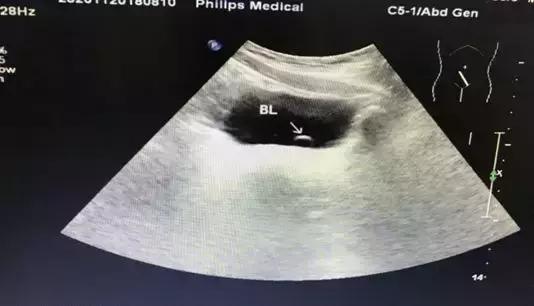

2018.8.14以发热待查收入我院儿科,入院查体T37.6℃,抗链“O”918IU/ml,泌尿系B超提示:左侧输尿管囊肿 初步诊断:1、链球菌感染,2、左侧输尿管囊肿。头孢唑啉1.5g bid ivgtt;